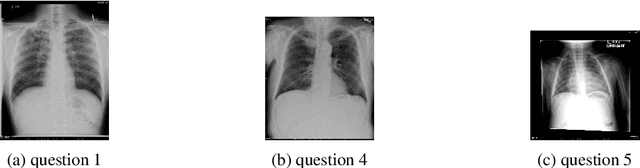

Abstract:Among all the sub-sections in a typical radiology report, the Clinical Indications, Findings, and Impression often reflect important details about the health status of a patient. The information included in Impression is also often covered in Findings. While Findings and Impression can be deduced by inspecting the image, Clinical Indications often require additional context. The cognitive task of interpreting medical images remains the most critical and often time-consuming step in the radiology workflow. Instead of generating an end-to-end radiology report, in this paper, we focus on generating the Findings from automated interpretation of medical images, specifically chest X-rays (CXRs). Thus, this work focuses on reducing the workload of radiologists who spend most of their time either writing or narrating the Findings. Unlike past research, which addresses radiology report generation as a single-step image captioning task, we have further taken into consideration the complexity of interpreting CXR images and propose a two-step approach: (a) detecting the regions with abnormalities in the image, and (b) generating relevant text for regions with abnormalities by employing a generative large language model (LLM). This two-step approach introduces a layer of interpretability and aligns the framework with the systematic reasoning that radiologists use when reviewing a CXR.